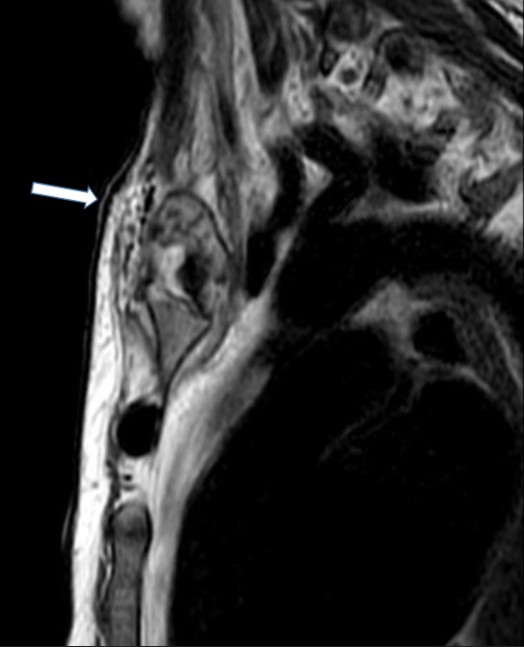

MRI of the chest showed findings consistent with osteomyelitis, including bone irregularities, edema, subchondral erosions of the right sternoclavicular joint, synovitis, and inflammatory joint changes (Fig. 2- 4).

Figure 2. Sagittal magnetic resonance imaging (POS-DIXON) (Multi-Dixon). Lytic lesion with ill-defined contour and soft tissue edema (stenoclavicular)

Figure 4. Coronal magnetic resonance imaging ESAG T2. Osteolytic lesion in sternal profile with periosteal reaction of the manubrio.